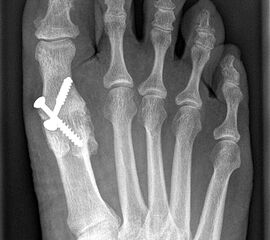

Gekreuzt eingebrachte Schrauben werden immer noch als kostengünstige Standardtechnik der Osteosynthese beschrieben und können bei kräftigen und stabilen Knochenverhältnissen und entsprechender Erfahrung prinzipiell verwendet werden 141516. Der Einsatz kanülierter Schrauben unter Durchleuchtung erleichtert die Operation.

Pseudarthrose: Verzögerte Knochenheilung und Pseudarthrosen treten je nach Osteosynthesetechnik unterschiedlich häufig auf. Bei Verwendung von Drähten oder Drahtcerclagen werden hohe Pseudarthroseraten von über 13% beschrieben, daher sollten diese Verfahren verlassen werden1021. Einzelschrauben bieten keine ausreichende Rotationsstabilität und werden daher nur noch selten verwendet. Korrekt eingebrachte gekreuzte Schrauben ergeben zwar bei primärem Hallux rigidus und guter Knochenqulität eine hohe Stabilität, sind jedoch bei osteopenischem Knochen und vor allem bei rheumatoider Arthritis oft unzureichend 141516. Die Rate an Pseudarthrosen kann hier durch Plattenosteosynthese mit interfragmentärer Zugschraube oder mit winkelstabiler Platte mit Gleit-/Kompressionsloch deutlich gesenkt werden 622. Nachteilig ist die Materialstärke der winkelstabilen Platte die zum Teil vermehrt aufträgt und daher gelegentlich die Metallentfernung notwendig macht.